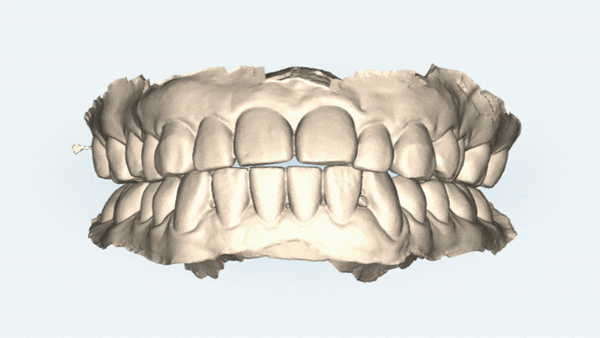

먼저 정확한 정밀진단을 위해 구강사진을 찍고 상담을 해드렸는데요 :)

초진 구강 내 사진

진단을 해보니 환자분의 치아상태는

앞니끼리 물리지 않는 '개방교합(Open Bite)' 상태셨어요

윗니와 아랫니 사이의 공간 보이시나요..?

분명히 어금니를 다문것 같은데 위 아랫니 사이가 떠 있어 보입니다.

정상교합은 사실 윗니가 아랫니를 2~3mm 정도 덮고 있어야 하는데 말이죠 ..